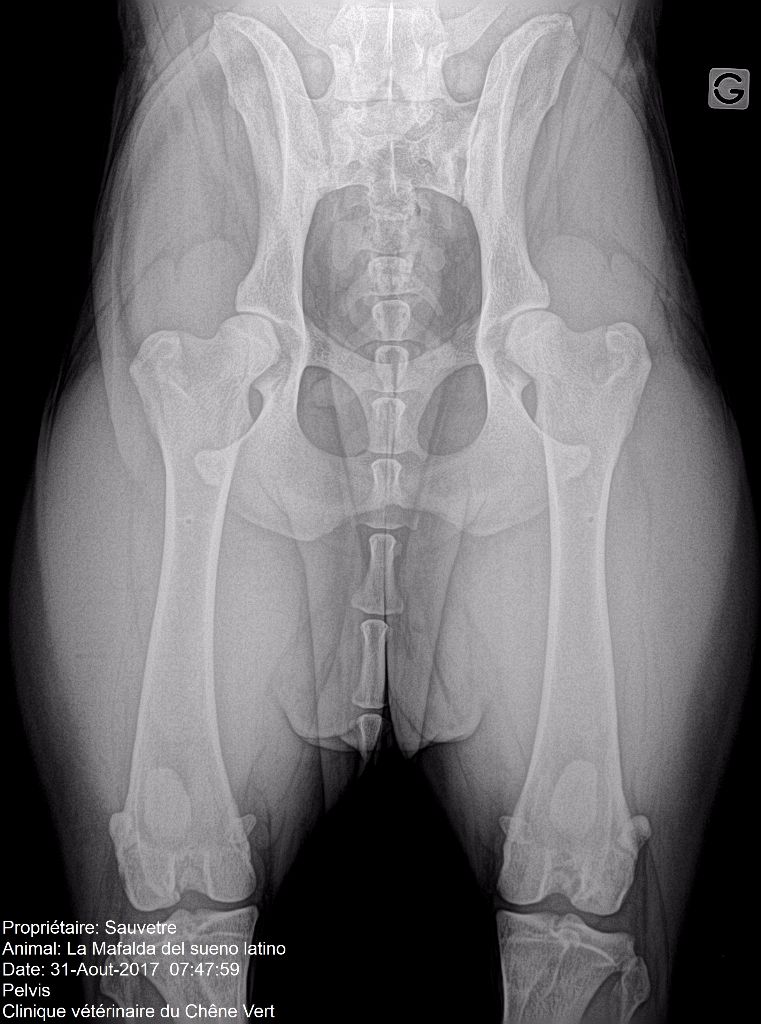

Radiographie hanches

Compte-rendu officiel dysplasie coxo fémorale

A.D.N. : identifiée + lien de parenté BAER TEST (surdité) : +/+ Dysplasie coxo-fémorale : A/A (lecture officielle du club de race AFSDA) Dysplasie des coudes : 0/0 (lecture officielle du club de race AFSDA) |